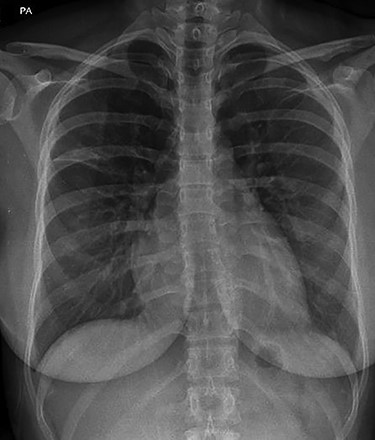

Initial investigations included a full blood panel with inflammatory markers (all within normal range) and a plain chest radiograph which demonstrated a mass in the right upper zone (Fig. 1). Computer tomography pulmonary angiogram (CTPA) scan demonstrated an 8 x 6.5 cm soft-tissue lesion within the right upper lobe (Fig. 2). This mass appeared to extend from the right hilum to the pleural surface and contained multiple small arterial branches. Her delivery date was brought forward pending further investigations. Positron emission tomography CT (PET-CT) demonstrated this lesion to be intensely fluorodeoxyglucose (FDG) avid (Fig. 3).

Plain chest radiograph demonstrating resolution of the right upper zone mass.